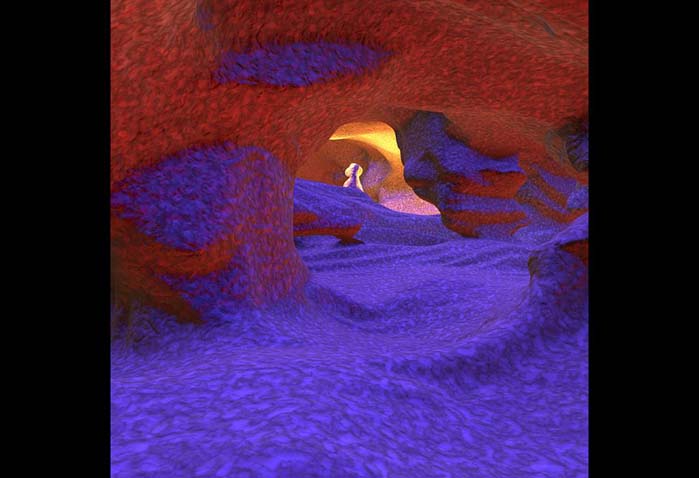

درون چشم انسان

در این تصویر درون رگهای پشت چشم انسان را میبینیم. این رگها خون شبکیه را تامین میکنند. از آنجا که خون با سرعت بسیار زیادی درون رگ حرکت میکند، در این تصویر قابل مشاهده نیست. به همین دلیل این هزارتو شبیه یک تونل زیرزمینی به نظر میرسد. نظر بیننده معمولا به نور انتها جلب میشود.

پزشکان از چنین تصاویری برای تشخیص علایم اولیهی بیماری چشمی استفاده میکنند. ارتفاع این تونلهای کوچک حدود ۱۰۰ میکرومتر (۰٫۱ میلیمتر) است.